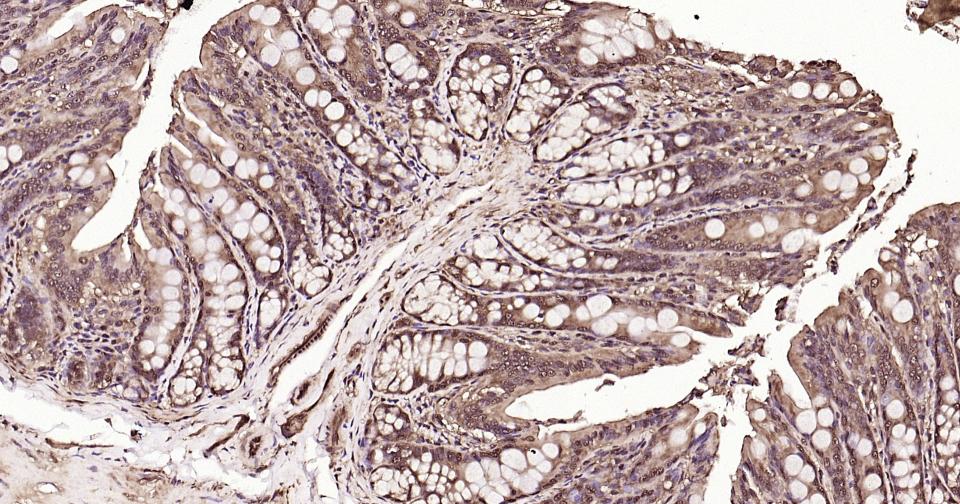

Paraformaldehyde-fixed, paraffin embedded Human Colon; Antigen retrieval by boiling in sodium citrate buffer (pH6.0) for 15 min; Antibody incubation with Ubiquitin Monoclonal Antibody, Unconjugated(bsm-63008R) at 1:200 overnight at 4°C, followed by conjugation to the bs-0295G-HRP and DAB (C-0010) staining and DAB (C-0010) staining.